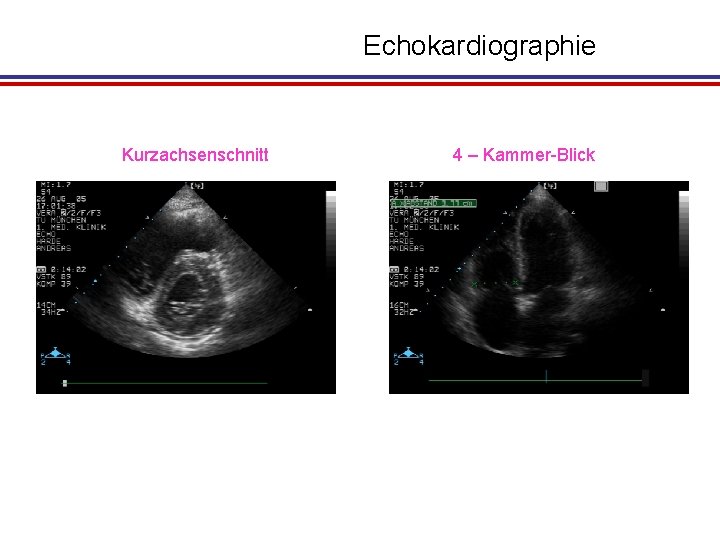

Echokardiographie Kurzachsenschnitt 4 – Kammer-Blick